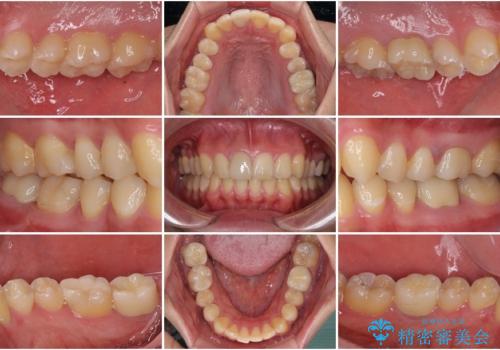

途中来院されない時期があったため、初診から終了まで期間がかかりましたが、根管治療を行った歯の根尖病変はいずれも改善を確認することができました。

口腔内の金属が全てなくなり、患者様には大変満足していただきました。